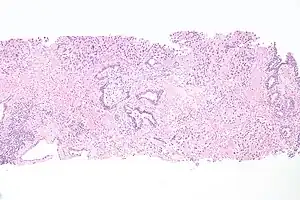

The cells lining the urethra (the epithelium) start off as transitional cells as it exits the bladder, which are variable layers of flat to cuboidal cells that change shape depending on whether they are compressed by the contents of the urethra.[12] Further along the urethra there are pseudostratified columnar and stratified columnar epithelia.[12] The lining becomes multiple layers of flat cells near the end of the urethra, which is the same as the external skin around it.[12]